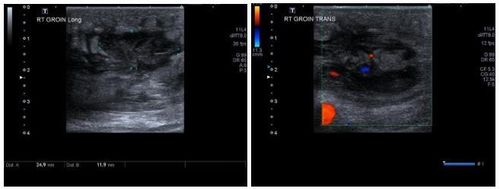

4.1. Siêu âm

- Ổ tụ dịch trống âm hoặc giảm âm hình tròn.

- Có thể có vỏ bao bọc có hồi âm, nhưng thường thì đường bờ không rõ ràng.

- Có thể thấy vách ngăn, cặn lắng, hoặc thậm chí có khí bên trong trung tâm ổ tụ dịch.

- Khi nén ép bằng đầu dò, có thể tạo ra chuyển động hoặc cuộn xoáy của các chất bên trong ổ áp xe.

- Hình ảnh đá cuội của mô dưới da xung quanh do phù nề của viêm mô tế bào kèm theo.

- Siêu âm Doppler thấy được hình ảnh tăng tưới máu ở mô mềm xung quanh ổ tụ dịch, không có tín hiệu Doppler bên trong ổ dịch.

Hình 2. Hình ảnh siêu âm vùng bẹn của bệnh nhân nam 25 tuổi: Mô mềm vùng bẹn phải dày lên, phù nề. Hình ảnh ổ giảm âm với các cặn lắng bên trong, không có tín hiệu Doppler bên trong ổ áp xe.